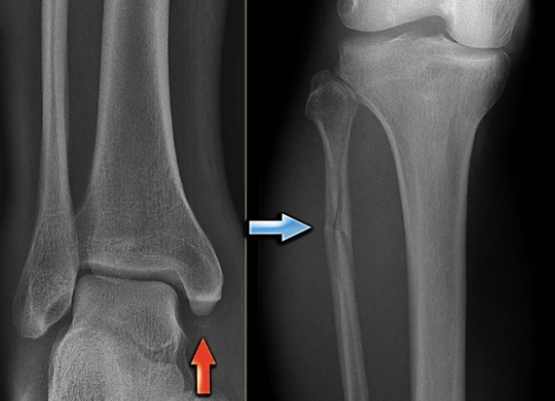

骨裂多久會好是許多患者最關心的問題。本文從專業角度詳細解析骨裂康復時間,包括輕微到嚴重骨裂的恢復期、影響因素、標準治療流程,並提供實用技巧加速康復。無論你是剛受傷還是正在康復中,都能找到解答常見疑問的完整指南,幫助你順利度過骨裂恢復期。